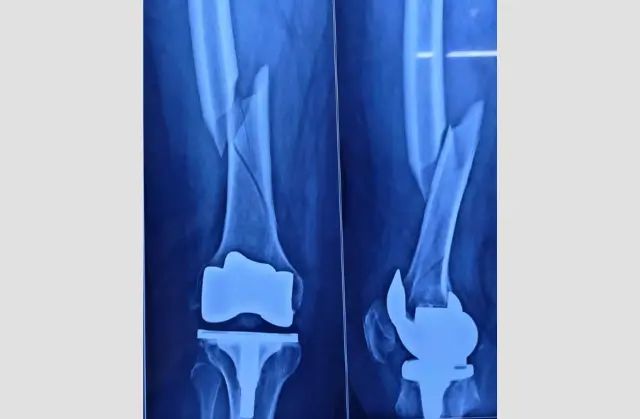

Meet Your Surgeon Dr. Shreyas Zalariya is a highly distinguished Orthopedic Consultant and Joint Replacement & Arthroscopy Surgeon. Having undergone rigorous Australian training, he combines international surgical standards with a compassionate, patient-first approach.

With advanced fellowship training from Australia, Dr. Shreyas Zalariya brings a global standard of orthopedic excellence to every patient. He specializes in cutting-edge, minimally invasive surgical techniques designed to minimize tissue damage and accelerate your return to an active life. Whether it is a complex joint replacement or a sports-related arthroscopy, Dr. Zalariya’s approach combines clinical precision with a deep commitment to long-term patient mobility and wellness.